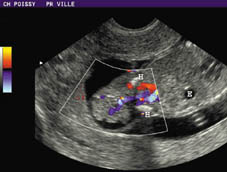

Doppler color. Estudio de la vascularización tumoral.